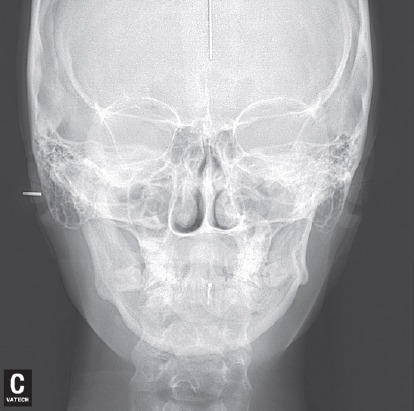

Рентгеноцефалометрический анализ боковых телерентгенограмм (ТРГ) (рис. 5 а, b) выявил у обоих пациентов верхнюю и нижнюю ретро- и микрогнатию, ретрузию верхних резцов, увеличение выпуклости лицевого профиля, лица, заднее положение подбородочного отдела. Анализ ТРГ в прямой проекции, выполненной пациентке Ж. по показаниям, — асимметрию нижней челюсти, выражающуюся в смещении подбородочного отдела влево и разнице в длине ее ветвей.

Рис. 6. Прямая телерентгенограмма пациентки Ж.

Fig. 6. Direct teleradiograph of patient Zh.